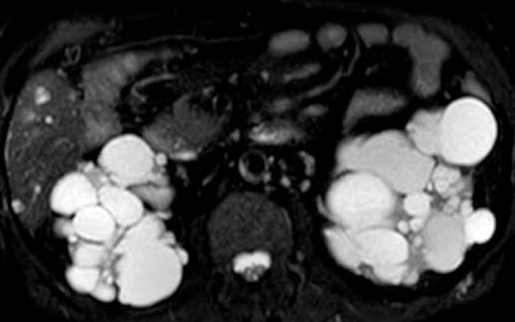

MRCP image confirms the absence of gallbladder and a normal biliary tree (Courtesy Dr. V. Penopoulos)